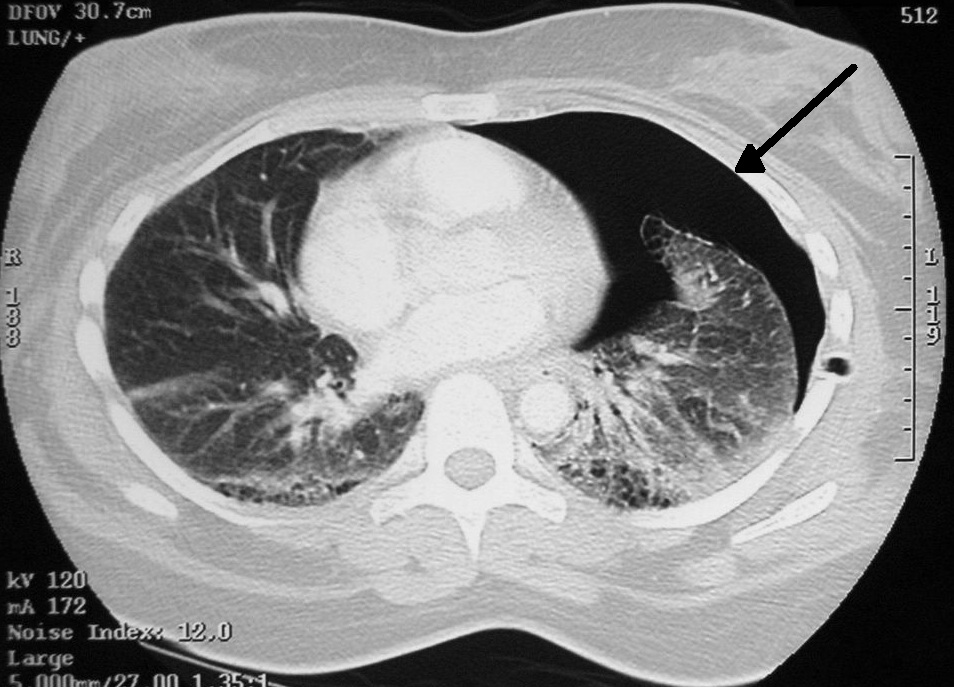

흉부 방사선 사진 촬영으로 진단할 수 있다. 흉부 X선 검사에서 혈관 음영을 동반하지 않는 허탈된 영역은 기흉으로 의심된다.[72] 최대 흡기(숨을 참음) 중에 촬영한 일반 흉부 방사선 사진이 가장 적절한 첫 번째 검사이다.[30] 만기 중에 정기적으로 촬영하는 것은 이점이 없을 것으로 여겨지나,[31] 임상적 의심이 높지만 흡기 방사선 사진이 정상으로 보이는 경우 기흉을 감지하는 데 유용할 수 있다.[32]

흉부 CT을 통해 비교적 큰 낭포라면 위치를 확인할 수 있다.[72] 폐기포를 정확히 확인하기 위해 흉부 CT를 실시한다.[15] CT 스캔은 기흉의 크기를 보다 정확하게 결정할 수 있지만, 이 상황에서 루틴하게 사용하는 것은 권장되지 않는다.[33]